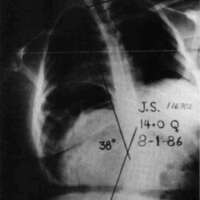

Let us now look at two examples were these stabilizing schemes have been simultaneously applied. Fig. 10a is a photo of a 12 year old boy with muscular dystrophy, sitting as he was presented to us. Fig. 10b shows the sitting support system properly applied. The corset is entirely independent; it is not attached to the seat. Fig. 10c and Fig. 10d compare his A-P spine x-rays without and with the orthotic system. The lateral tilt of his pelvis is reduced from 30 degrees to 14 degrees. The Cobb angle of his scoliosis was reduced from 65 degrees to 35 degrees. Curve control of this magnitude is not unusual as long as the deformity is still flexible. Fig. 11a is the x-ray of J.S., a 14 year old girl with cerebral palsy. She presented a right thoraco-lumbar scoliosis of 38 degrees and a rightward pelvic tilt of 8 degrees. Her shoulders were tilted 13 degrees to the left partly because she used her right arm for propping to avoid falling to the right. We provided her with a soft corset and the Gillette Sitting Support Orthosis. The Sitting Support Orthosis was to provide pelvic control and bilateral "propping" support. It had no head rest or anterior support. The x-ray taken just after fitting shows pelvic tilt reduced to 2 degrees (Fig. 11b), the Cobb angle of the scoliosis reduced to 22 degrees, and shoulders leveled. Both hands were free to function, and she said she could breathe deeper.

Figure 10c. A-P spine x-rays without the orthotic system.

Figure 10d. A-P spine x-rays with the orthotic system.